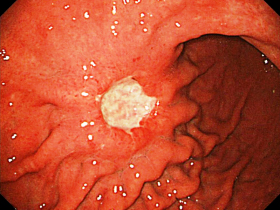

- Гастроскопия. Эндоскопическое исследование позволяет осмотреть внутреннюю поверхность органа и взять пробу патологической ткани для анализа.

Развитие онкологического процесса начинается с нулевой стадии рака желудка, на которой дисплазия преобразуется в злокачественные клетки. Этот этап называют раком «in situ», т.е. «на месте». Новообразование обладает крайне малыми размерами и обнаруживается случайно при эндоскопическом исследовании по поводу другого заболевания. Далее процесс развивается по следующим стадиям.